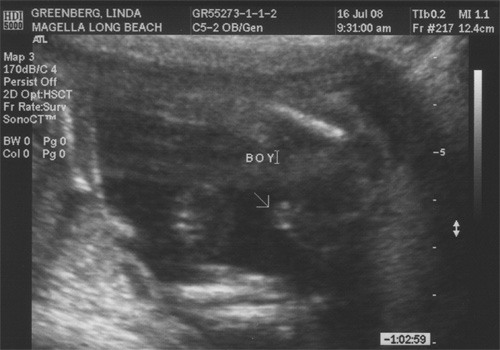

The ultrasound technician did tell us, as is illustrated by the picture below, settling all disputes or guesses.